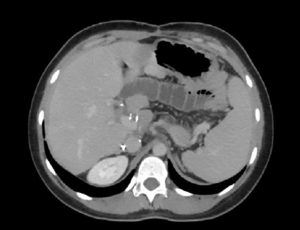

Spontaneous Resolution of Infected Pancreatic Necrosis after Fistulization into Upper Gastrointestinal Tract

We have recently published a case of spontaneous gastric decompression and resolution of an infected walled-off pancreatic necrosis (WOPN). According to the so-called “step-up approach”, which is a staged and multidisciplinary approach for the treatment of necrotizing pancreatitis, we have outlined the need of treating WOPN and their complications according to the clinical course of the patients and not only to radiological and laboratory findings.